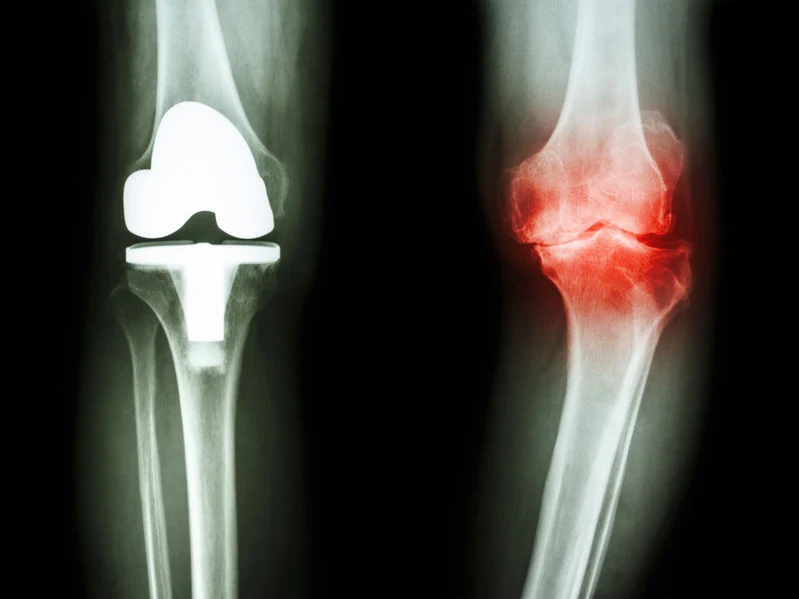

Osteoartroza to choroba kostno-stawowa polegająca na zwyrodnieniu stawów – najczęściej biodrowych i kolanowych, ale też stawów rąk i stóp. W początkowych stadiach proces chorobowy obejmuje jedynie chrząstkę stawową, z czasem dotyka mięśni, warstwy podchrzęstnej kości, ścięgien więzadeł, a nawet sąsiednich stawów.

W leczeniu osteoartrozy bardzo ważny jest czas – im mniejsze są zmiany zwyrodnieniowe, tym większa jest szansa na pełną sprawność stawu. Podstawowym badaniem diagnostycznym jest rtg stawu. Lekarz w zależności od stadium rozwoju choroby zaleci leczenie niefarmakologiczne lub farmakologiczne. W niektórych przypadkach konieczne jest leczenie operacyjne.

W przypadku silnego bólu i obrzęku stawu stosuje się niesteroidowe leki przeciwzapalne lub, gdy to nie pomoże, bezpośrednio do stawu podaje się glikosteroidy. Kiedy stawu nie da się już uratować, wykonuje się endoprotezoplastykę – wszczepienie endoprotezy. W leczeniu i profilaktyce osteoartrozy ważna jest także zbilansowana dieta, bogata w pełnowartościowe białko (warzywa strączkowe, chude mięso, ryby morskie, chudy nabiał), błonnik (pieczywo pełnoziarniste) i witaminy z grupy B.